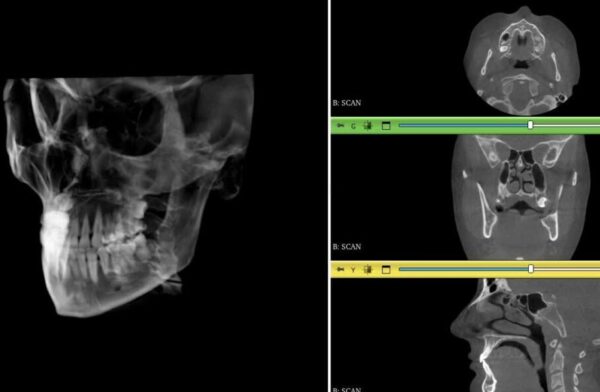

VELMENI for Dentists® 3D

Create 3D realizations of 3D/CBCT scans in minutes. Reveal nerves, sinuses, TMJ, airways, and important anatomical features for medical detections, treatment planning, and patient education.